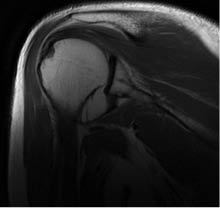

Imagen: se realizó una radiografía con proyección anteroposterior (Figura 1), y una resonancia magnética simple de hombro izquierdo (Figuras 2 y 3) y se realizó el diagnóstico de luxación glenohumeral, inestabilidad anterior de hombro, lesión de Bankart y lesión de Hill-Sachs.

En las imágenes tomadas antes del procedimiento quirúrgico se observa, en la primera radiografía simple de hombro izquierdo en proyección anteroposterior, una luxación de la articulación glenohumeral, mientras que en la resonancia magnética simple (cortes axial y coronal), se detecta una lesión de Hill-Sachs y una lesión de Bankart, las cuales de acuerdo con la literatura son característica en los pacientes con luxación glenohumeral e inestabilidad anterior de hombro.

Figura 2